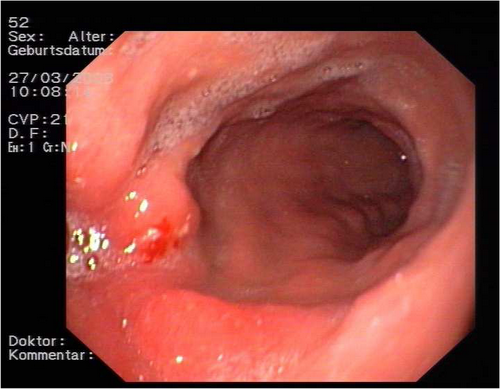

Ein halbes Jahr später zeigte die durchgeführte ÖGD einen Polypen im Bereich der Anastomose. Es wurden daraufhin mehrere PE entnommen.